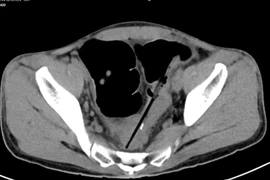

Các bác sĩ Bệnh viện Bạch Mai vừa phẫu thuật cho người đàn ông nuốt nhiều dị vật gây biến chứng thủng đại tràng. Người bệnh được chẩn đoán mắc hội chứng Pica - thích ăn các đồ vật.

Trung tâm Phẫu thuật tiêu hóa - Bệnh viện Bạch Mai vừa phẫu thuật một trường hợp người bệnh nuốt nhiều dị vật gây biến chứng thủng đại tràng. Người bệnh được chẩn đoán mắc hội chứng Pica (hội chứng thích ăn các đồ vật không phải thức ăn).